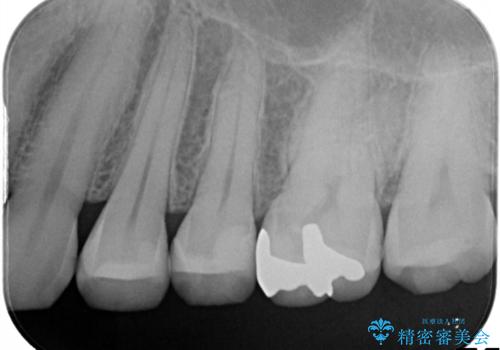

古い材料を除去すると中で虫歯が進行していたため、顕微鏡下で虫歯を除去した後セラミックインレー、PGAインレーにて修復治療を行いました。

すべての処置で拡大鏡及び顕微鏡を用いるため高い精度で治療を行うことができます。